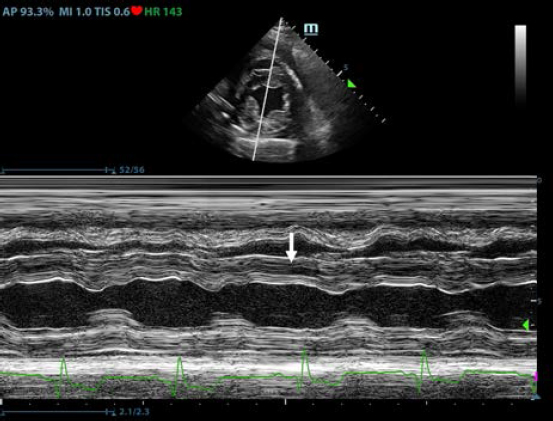

First, transthoracic echocardiogram findings were a small amount of circumferential tamponating pericardial effusion (Fig. 1) and a severe hyperechoic pericardial thickening (10.2 mm) (Fig. 2). The right atrium was normal in size and there was collapse during systole. There was mild septal flattening seen on short axis view of the left ventricle. A short-axis left ventricular M-mode showed posterior displacement of the interventricular septum during late diastole at the time of atrial systole (Fig. 3). The epicardium and pericardium had a hyperechoic appearance with a thin, shaggy layer of heterogeneous echogenic material lining the surface of each (Fig. 1, Supplementary Video I). Pericardiocentesis was not recommended at this time given that the patient was minimally clinically and hemodynamically affected. Few hours later, a second echocardiographic examination, after stabilization of left ventricular volume with intravenous (IV) lactate ringer solution at maintenance rate, showed a worsening of pericardial thickness (13 mm) and an increase in pleural effusion. Furthermore, there was a >25% mitral inflow variation noted with respiration. In addition, there was >30% tricuspid inflow variation with respiration, signs of CP. During the second echocardiography, the patient appeared to be slightly dyspneic due to the increased thoracic effusion.

Fig. 3. Transthoracic echocardiogram – M-mode right parasternal short axis view of the left ventricle. Note the paradoxic septal motion (white arrow) characterized by diastolic posterior motion of the interventricular septum toward the left ventricular free wall.